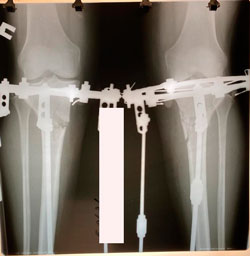

Исходник - 50 лет.

Дата операции - 15.12.2020

Вложения

image-26-12-20-12-00.jpg

image-26-12-20-12-00-1-(1).jpg